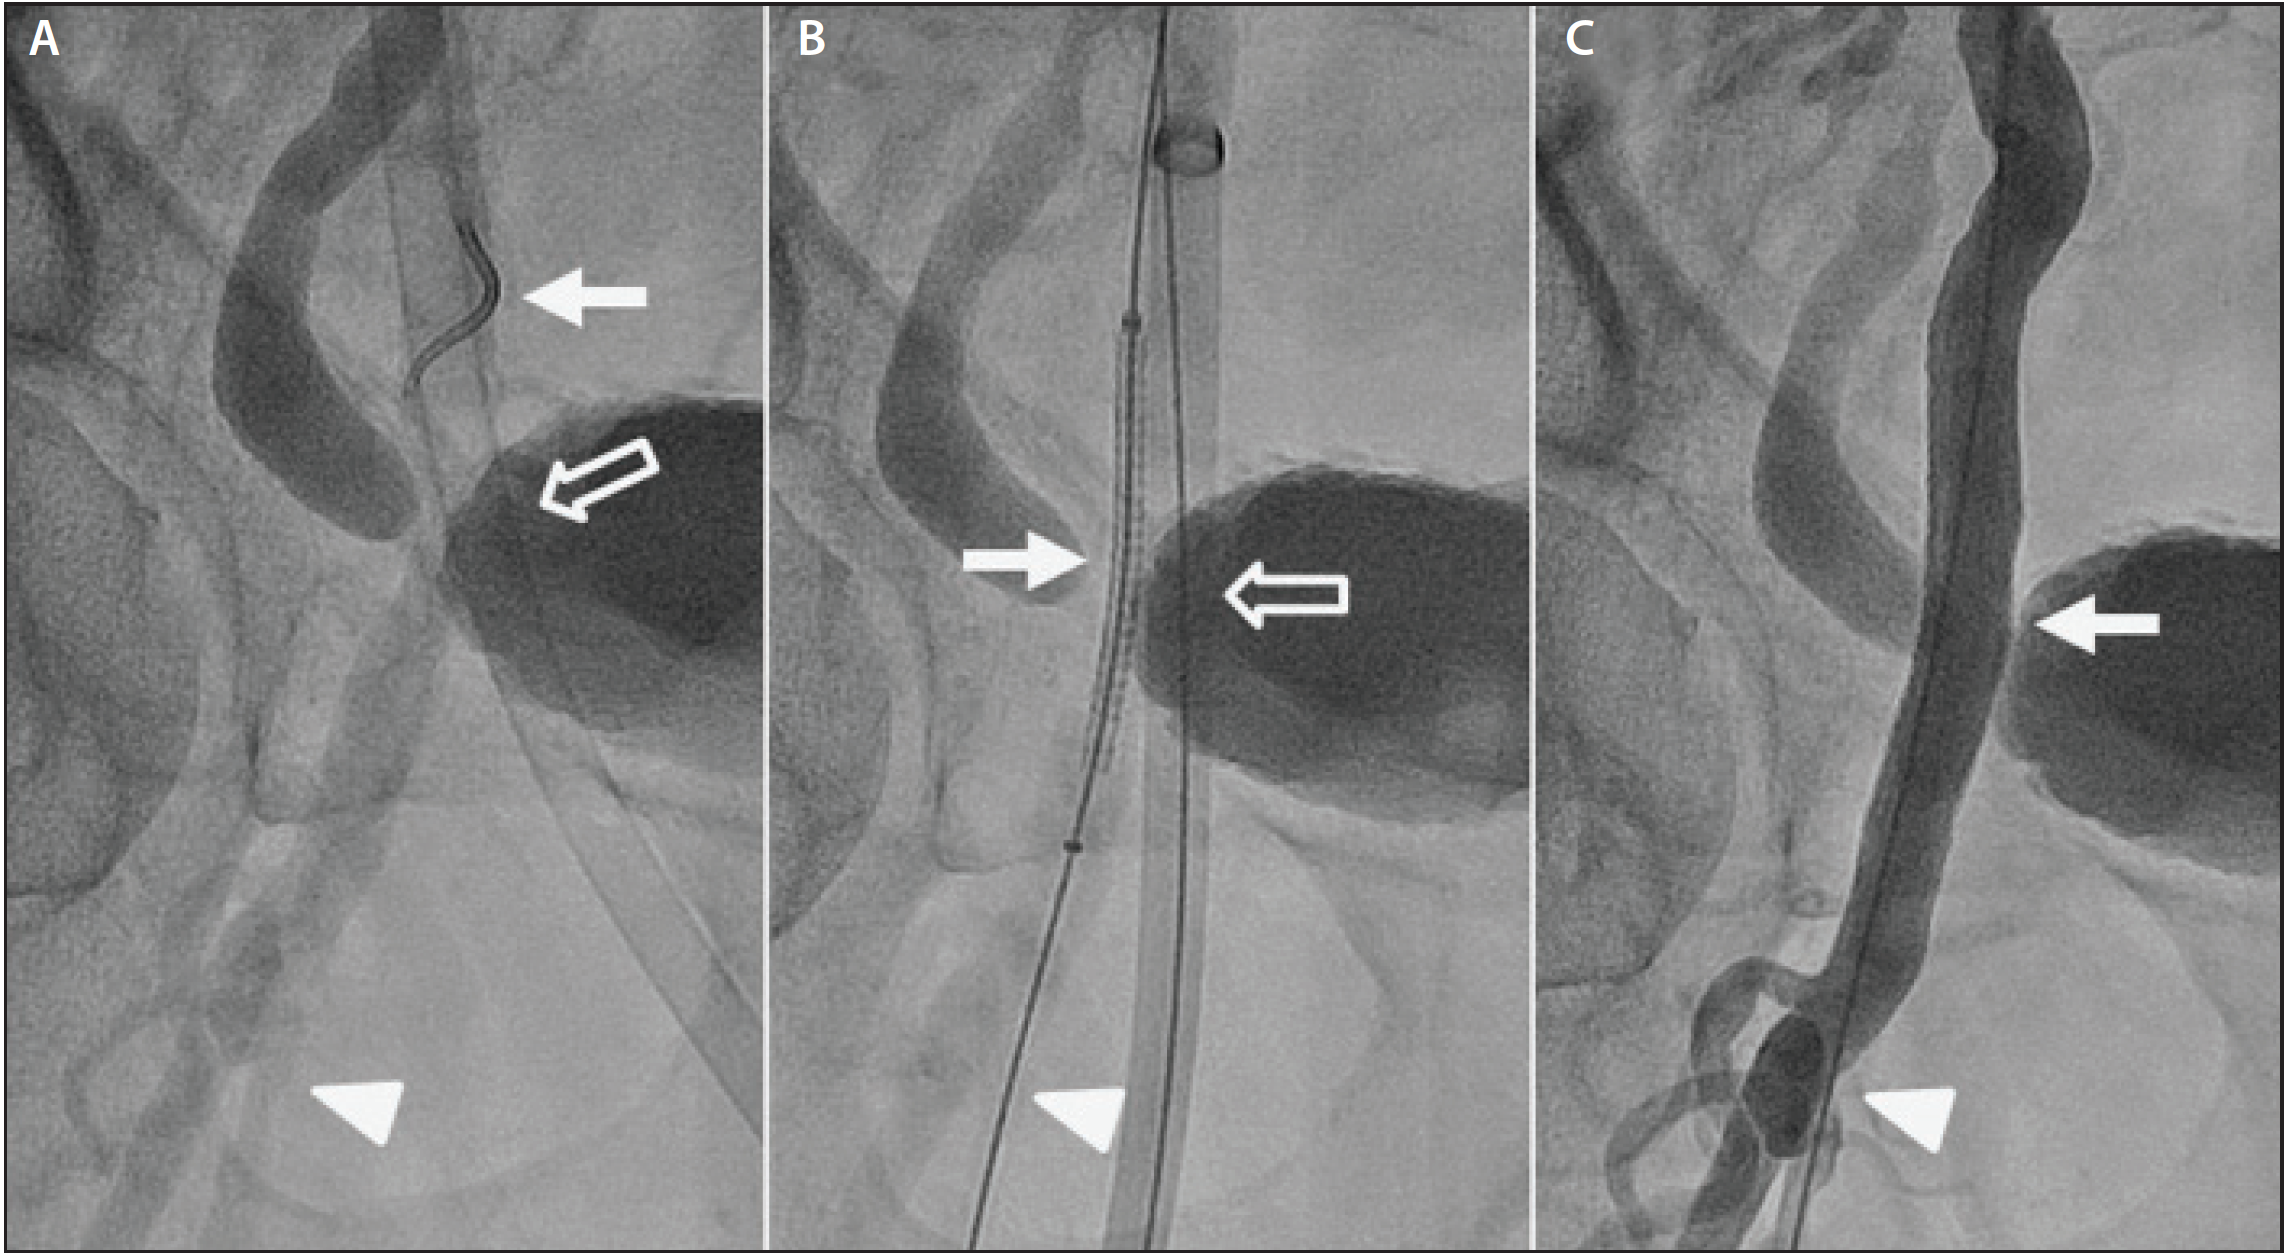

Figure 2. Iatrogenic occlusion of the right common femoral artery after tightening of the two pairs of sutures from the two Perclose ProGlide vascular closure devices deployed for preclosure (arrow) (A). Atherotomy balloon angioplasty (arrowhead) performed using a peripheral cutting balloon advanced through the contralateral femoral artery access sheath (B). Successful dilatation of the occluded right common femoral artery (hollow arrow) with re-establishment of brisk flow to the distal vessels (C).

Definitive therapy. For hemodynamically significant obstructive lesions, balloon angioplasty of the stenotic segment can be safely performed. Figure 2A illustrates iatrogenic occlusion of the right common femoral artery. Atherotomy balloon angioplasty (Figure 2B) was successfully performed to recanalize the occluded segment and restore flow distally, as shown in Figure 2C. Provisional stenting with deployment of a nitinol self-expanding stent can be used to treat hemodynamically significant residual stenosis.